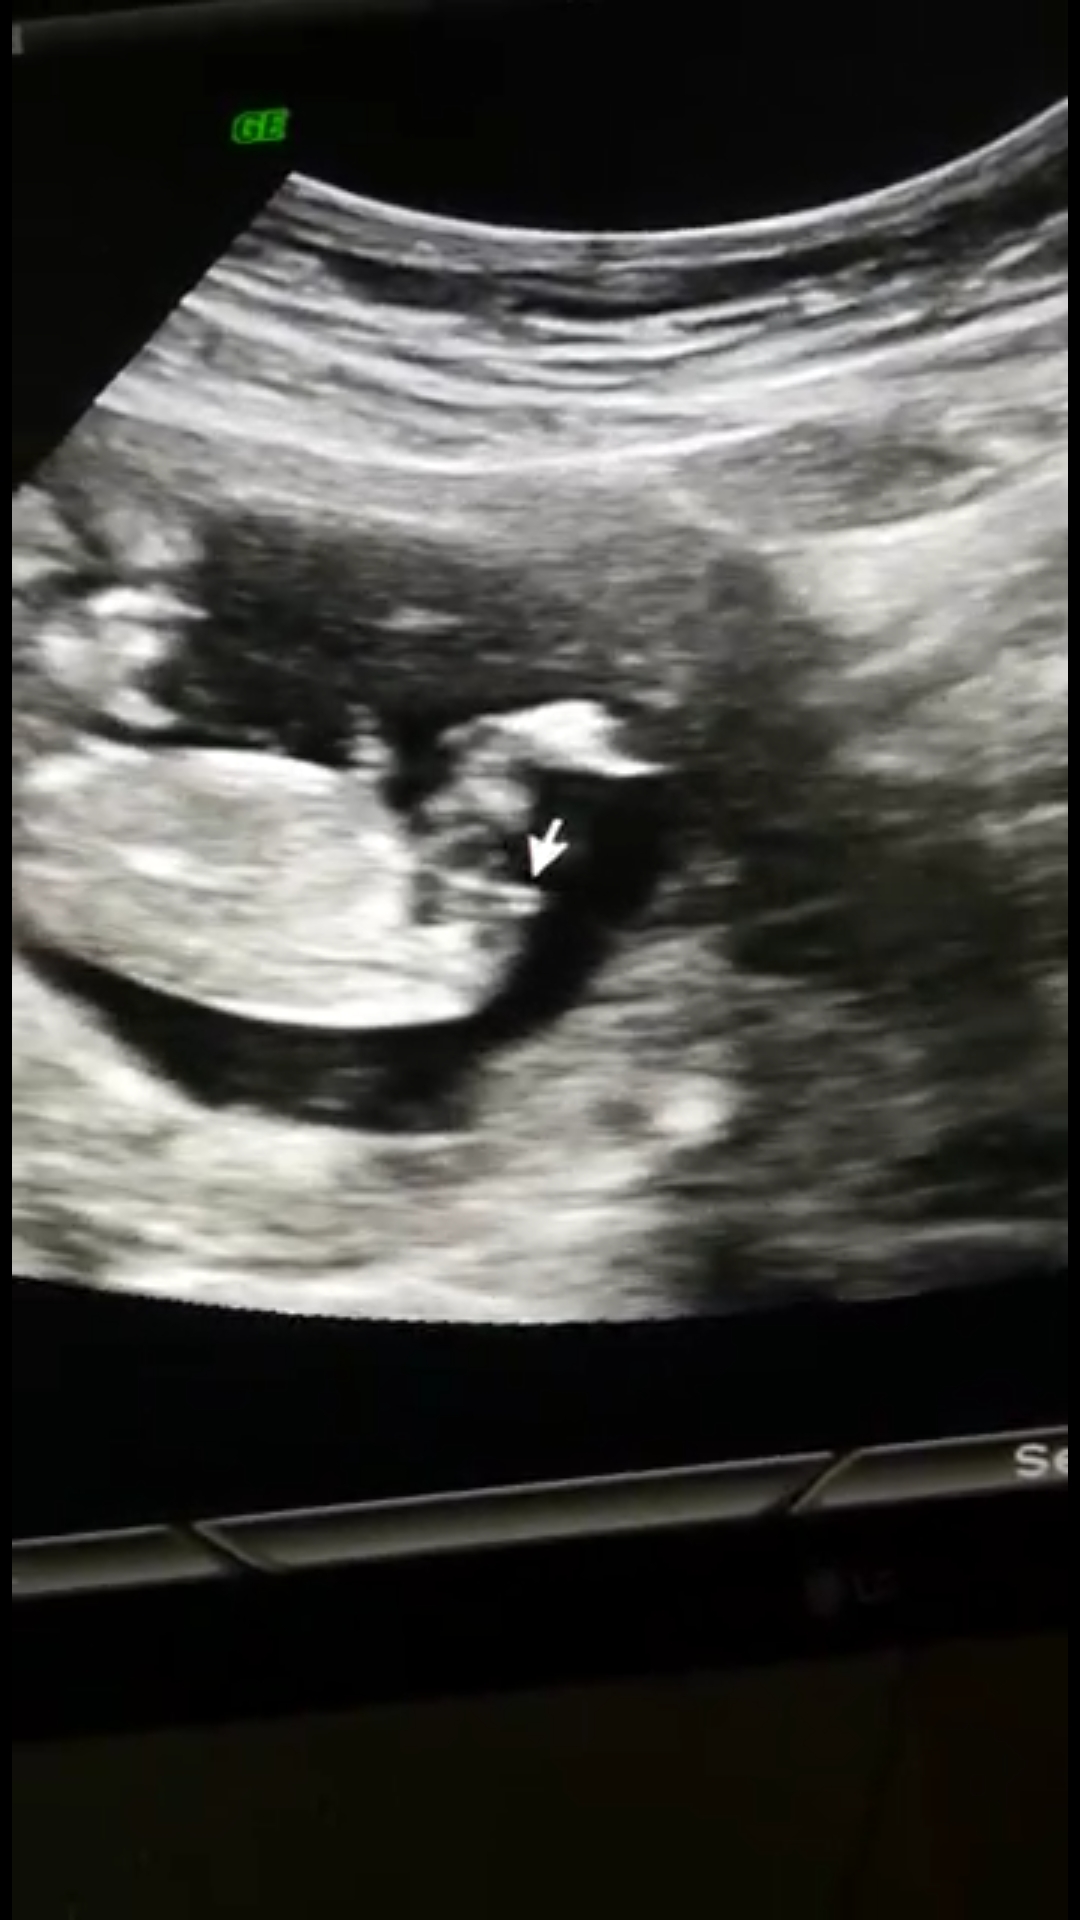

Canım. Benim bebiseme de bakar mısın 12+1Selamlar, Ultrason sonucuna göre cinsiyet tahmini var tabiki NUB TEORİSİNE GÖRE CİNSİYET başlıklı konumuzdan resimleri nasıl atacağınız ifade edilmiştir. Hemen konuda aşağıda yer alan özellikle cinsiyet belirlemede olması gereken çıkıntıların çıktısının olması gerekiyor. Bu resimlerin büyüğü var ise gönderin bize ya da linkini verdiğimiz konuya bakarak kendiniz de tahminde bulunabilirsiniz.

Vallahi ben uzman değilim ve Gaybı geleceği olacağı ancak Allah bilir ha illa yüzde verin diyor iseniz %52 kız diyelim![]()